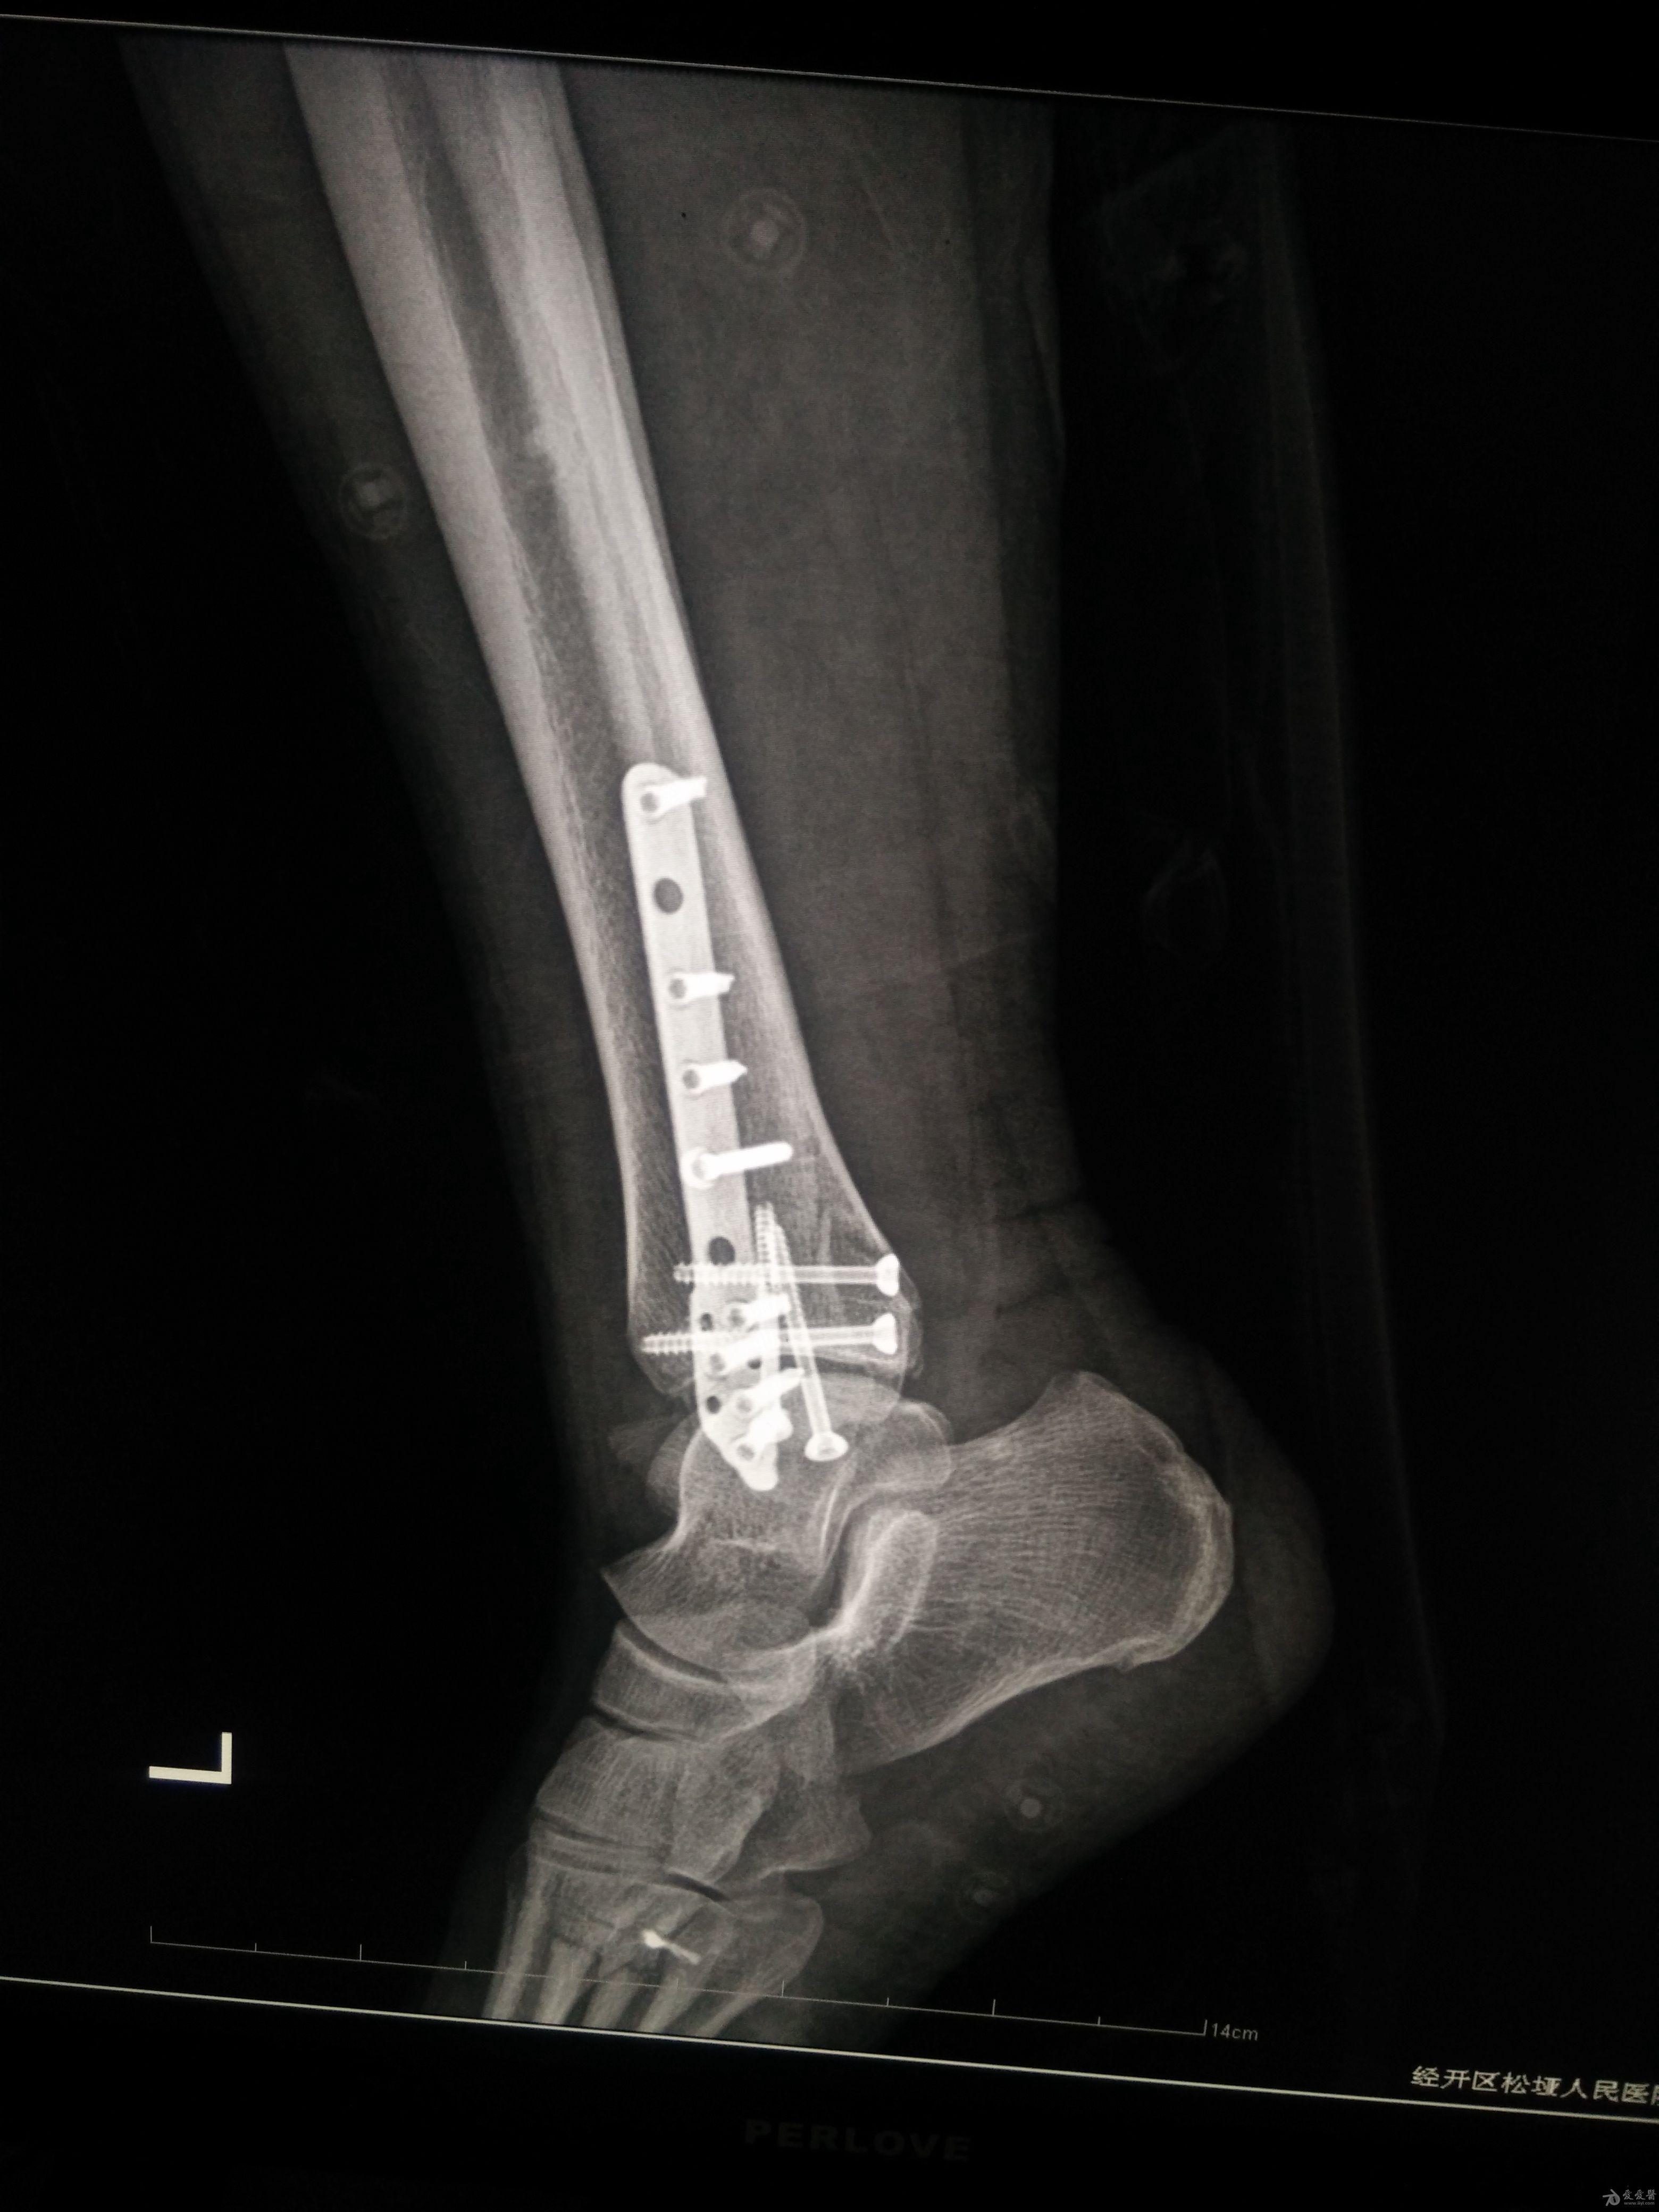

左三踝骨折手术治疗

患者女,外伤后左踝关节活动受限1小时入院,

入院后查体:左踝关节肿胀,活动受限,行DR及左踝关节CT检查,如下图,手术待肿胀消退后行手术治疗,目前愈合良好,请问问各位老师,好久可以下地呀, 下胫腓联合镙钉3个月取呀,

这个下胫腓螺钉真的没有必要打,另外后踝的两枚螺钉怪怪的,从后往前打的,看着钉子帽偏内侧,这个应该在外侧才对,